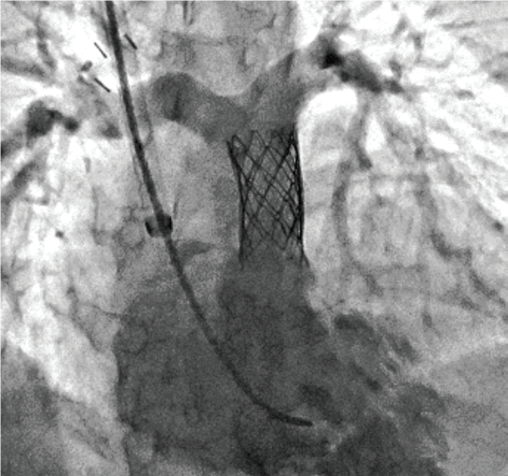

Stent Enhancer* забезпечує візуалізацію стента за рахунок придушення анатомічних структур та фонового шуму.

Stent Mode забезпечує покращену візуалізацію стента в реальному часі без необхідності додаткової окремої обробки або післяобробки.